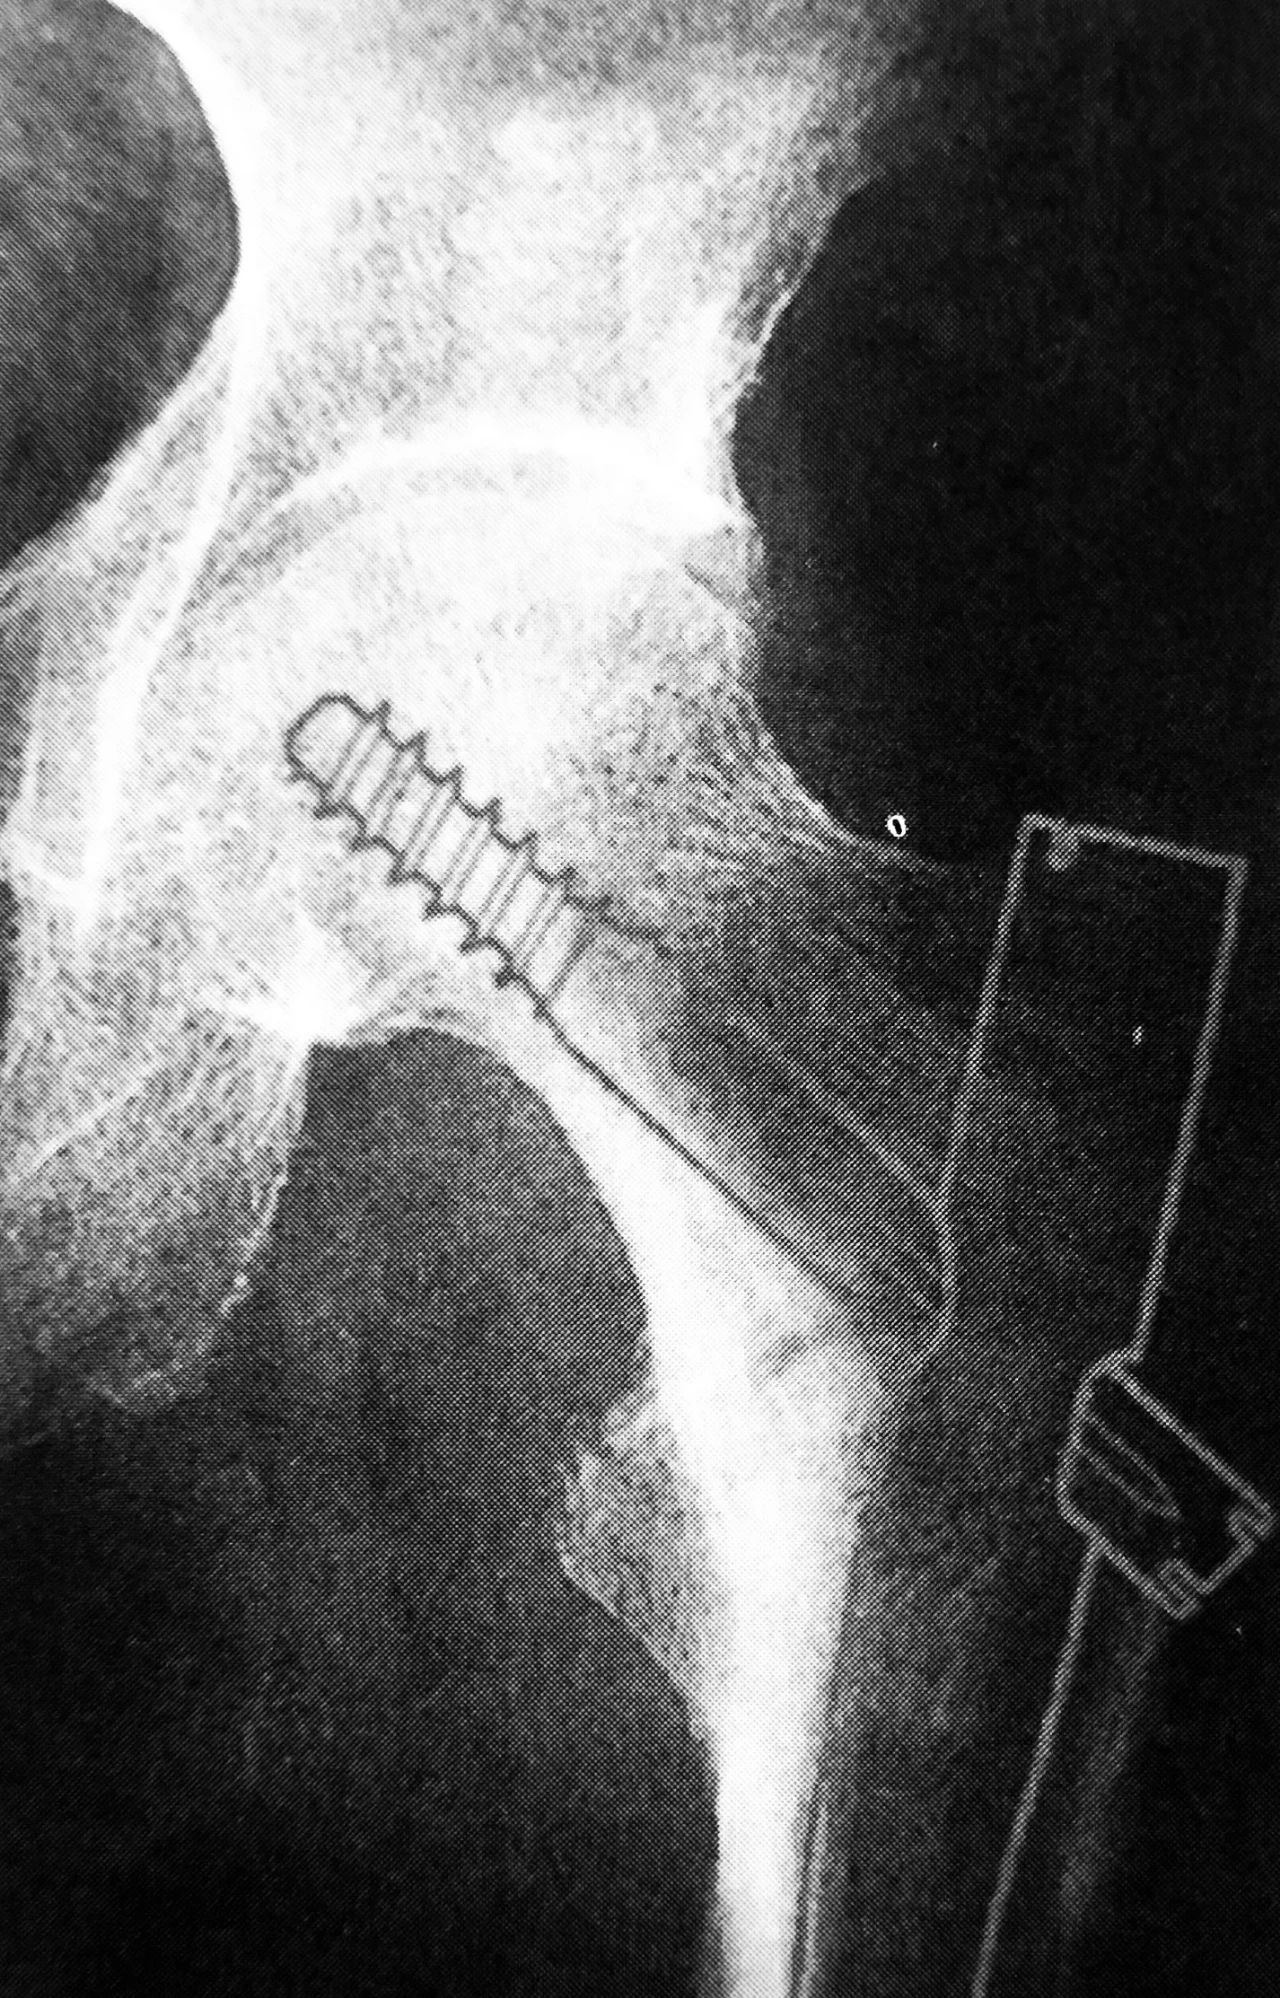

1. Gamma 钉

Gamma 钉适用于股骨颈基底至小转子水平以上的各种类型的骨折。Gamma 钉内固定技术除感染外无绝对禁忌证,伴有严重骨质疏松患者术后的早期活动需要一定的限制。

拉力螺钉的正确放置非常重要,其前提是首先安放好导针的位置,即正位必须与股骨颈轴线重叠或位其稍下方,侧位或斜位导针应在股骨颈中心。

A 拉力螺钉的安装;B 拉力螺钉的正确位置

拉力螺钉的置入,A 确定长度;B 阶梯钻钻孔 C 拧入拉力螺钉并加压

4. 股骨近端髓内钉

股骨近端髓内钉系统( proximal femoral nail system,PFN)是由AO内固定学会根据 Gamma钉原理改良设计而研制的用于股骨近端骨折治疗的髓内固定材料。PFN 适用于股骨颈基底至小转子以下 5cm 的骨折,也就是 AO 分类中 31-A的所有骨折和转子高位股骨干骨折。

其结构特点和优势:①主钉长 240mm,近端直径17mm,远端直径有10、11、12 三种规格可供选择;颈干角设计 130°,外翻角6°

②股骨头、颈内的螺钉有两枚组成,下方为直径 11mm 的主拉力螺钉,上方为直径 6.5mm 的防旋螺钉。这种防旋螺钉的设计能更有效的防止骨折断端的旋转。

③主钉远端可屈性的凹槽设计,远端锁钉孔距钉尖距离较长,最大程度地减少应力集中,降低主钉末端股骨干骨折的风险。

④主钉远端提供静态和动态两个锁钉孔。

PFN 主要并发症是防旋螺钉的向内侧切出近端静态交锁钉或向外退出,被称为「Z效应」。建议拉力螺钉的放置于股骨头软骨面下 0.5cm 以内,防旋钉钉尖与拉力螺钉钉尖位于同一水平线。同时拉力螺钉应尽量下移,贴近股骨距,以增加螺钉在骨质中的锚合力。